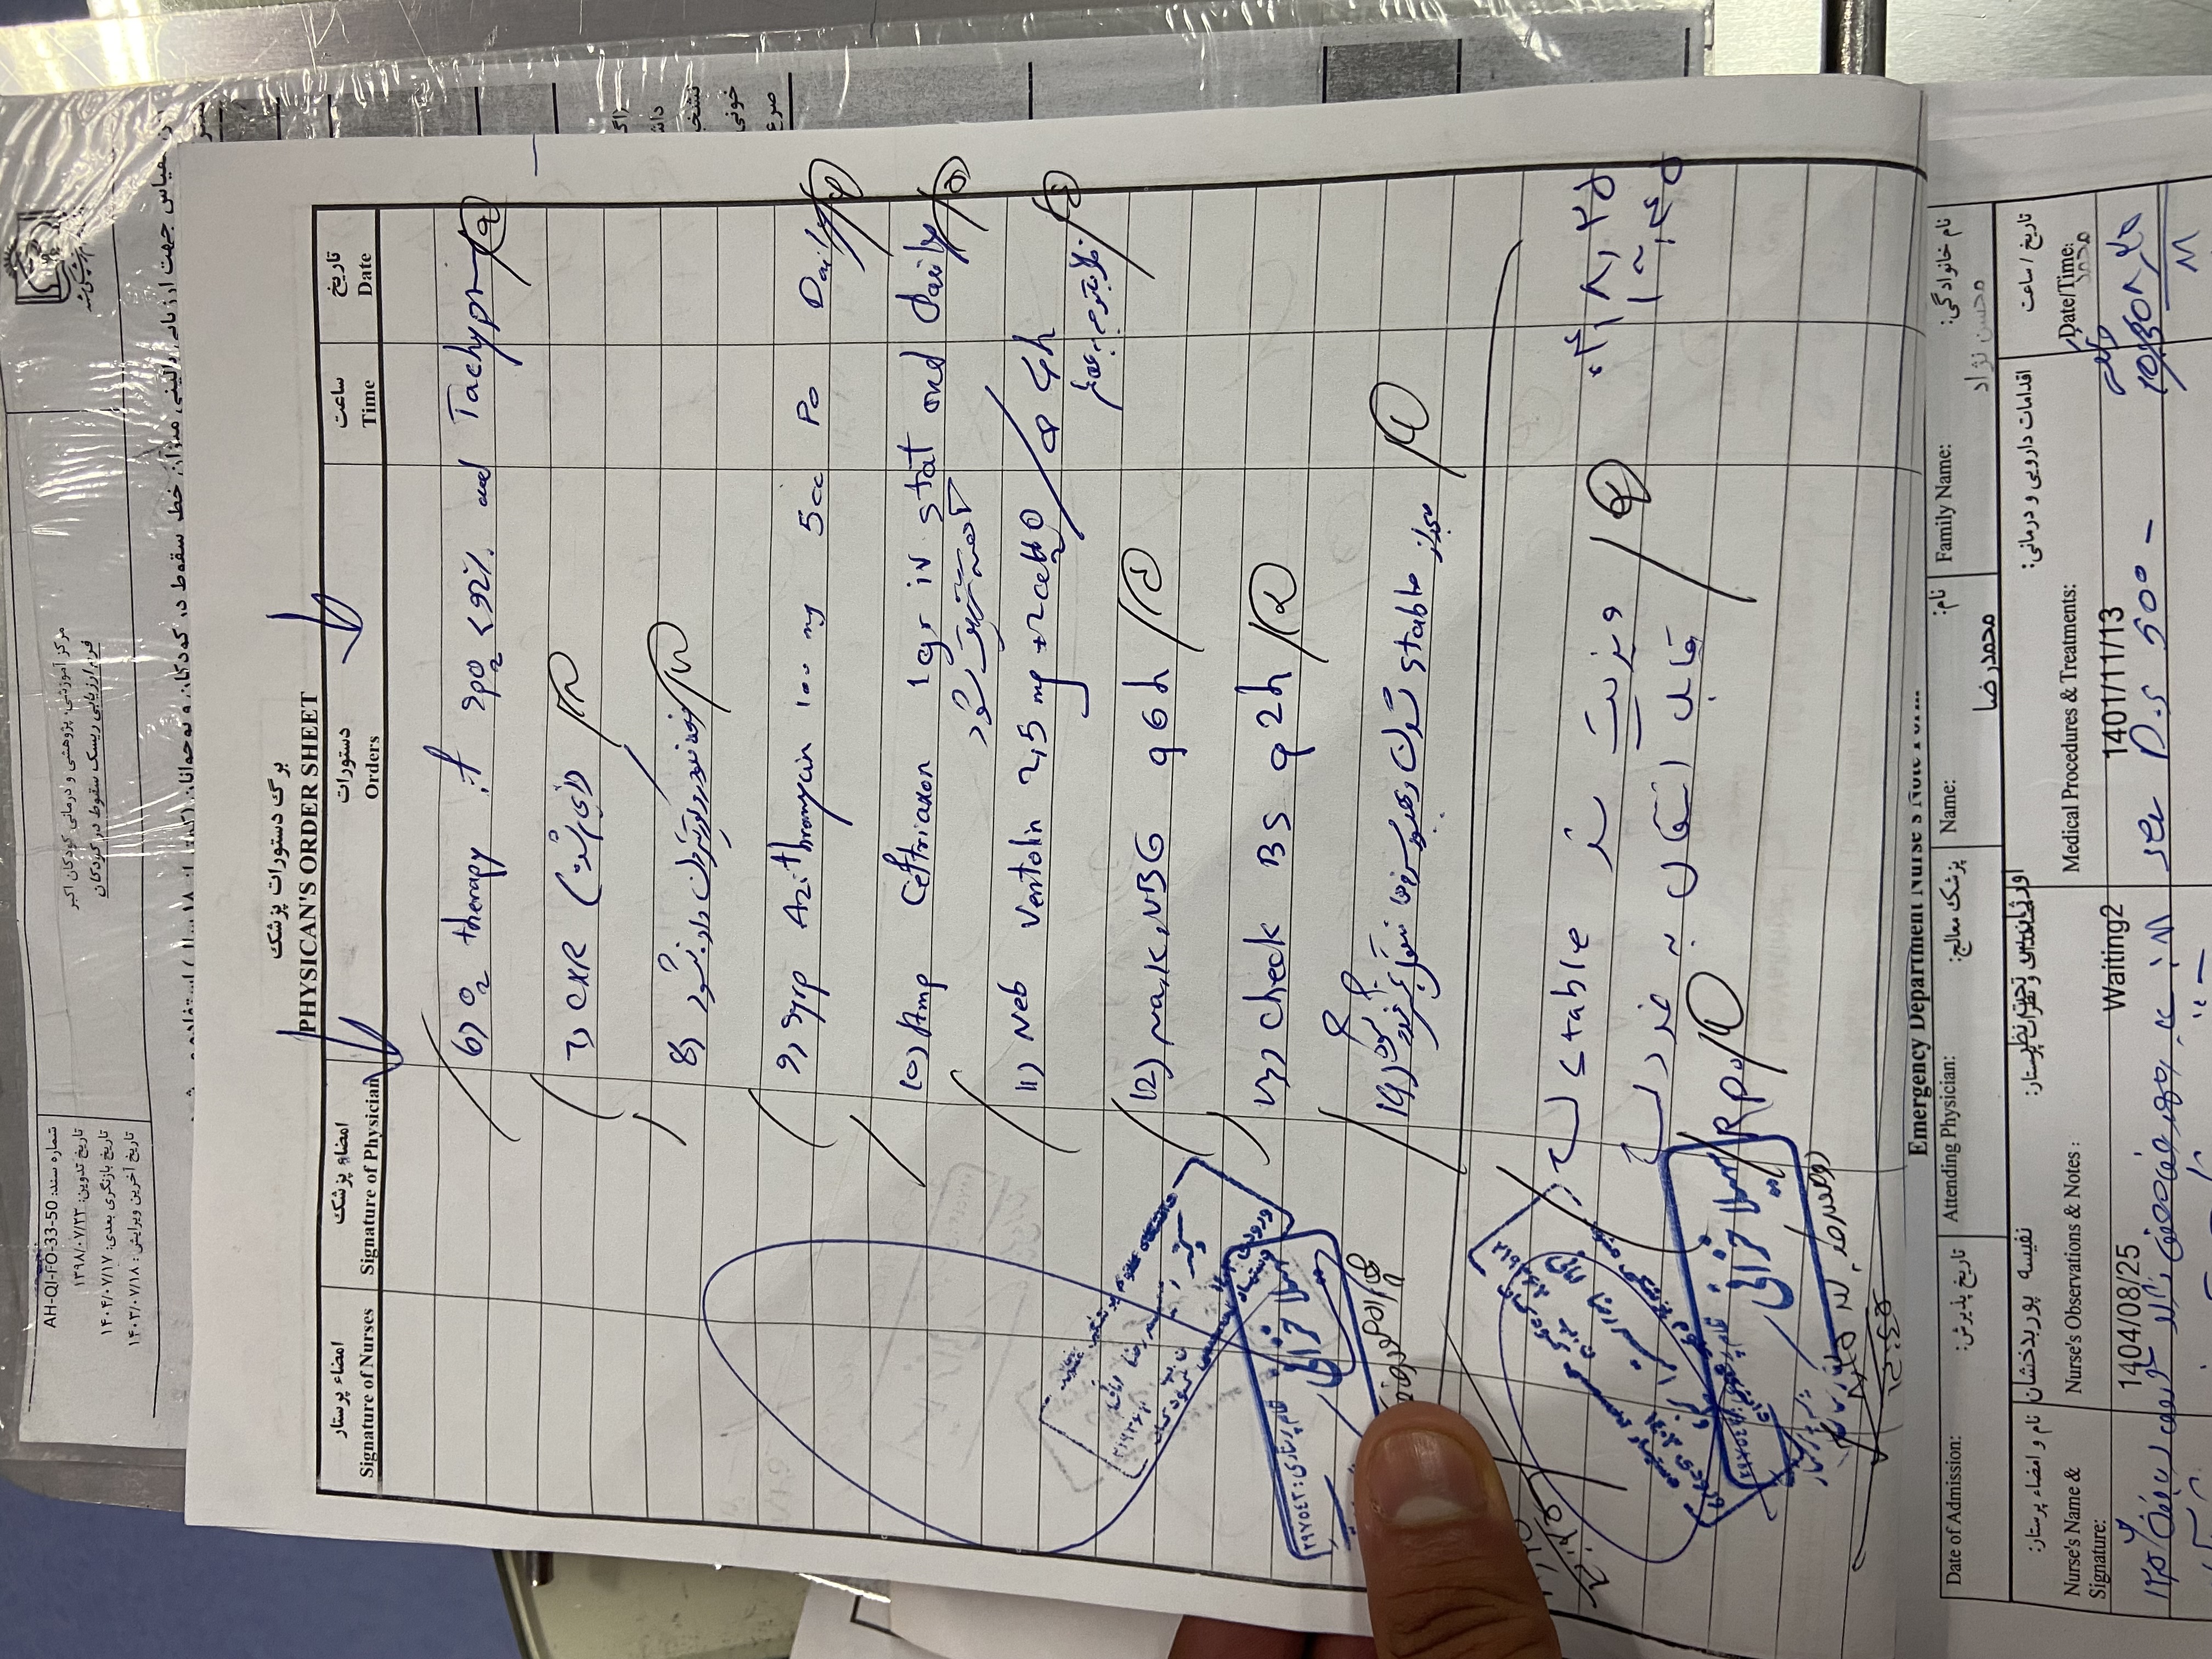

بیمار پسر ۲ سال ونه ماه مورد cah از ۱۷ روزگی تشخیص شده (با علایم اولیه poor feeding و تیرگی پنیس و لب وپتاسیم ۹ )با سرفه prوتب از دیشب شروع شده به اورژانس مراجعه کرده وهمچنین ۳ نوبت استفراغ داشته وابریزش بینی وسایقه بستری مکرر داشته با شک به گریز ادرنال بستری شدن

پسر 2ساله ونه ماه با تب وسرفه وابریزش و۳ بار استفراغ از دیشب به اورژانس مراجعه کرده مورد cah از ۱۷ روزگی تحت درمان با هیدروکورتیزون و فلودروکورتیزون بوده با شک به کریز ادرنال بستری شدن تاکی پنه وتاکی کاردی داشته

DDx

گریز ادرنال

پنومونی

برونشیت

سپسیس